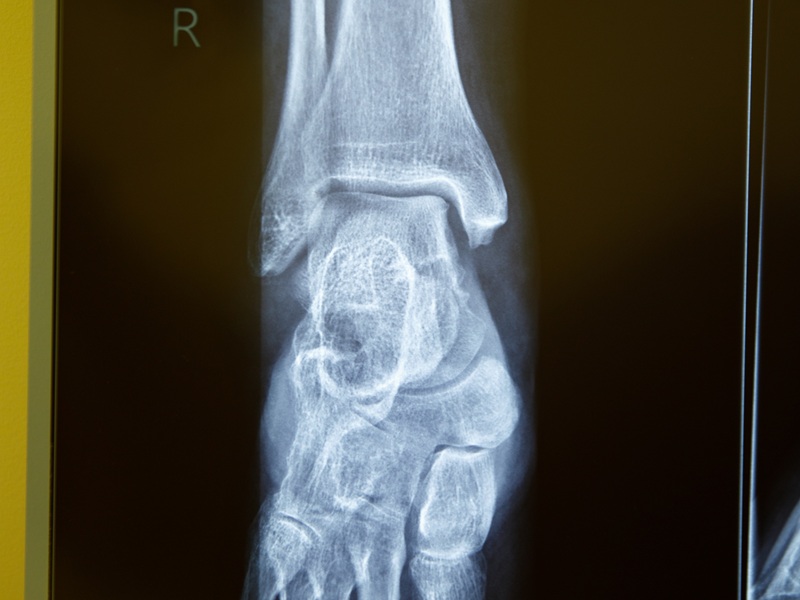

На відміну від рентгенографічного дослідження, за допомогою комп'ютерної томографії можна отримати тривимірне зображення гомілковостопного суглоба. Воно будується з окремих візуальних зрізів, які формуються під час покрокового сканування нижньої кінцівки. Знімки виходять більш точними і структури, зображені на них, можна розглядати за допомогою спеціальної програми на комп'ютері під різними кутами.

На знімках КТ гомілковостопного суглоба відображені таранна, велика та мала гомілкові кістки, навколишні м'які тканини. Можна виявити ознаки дегенеративних процесів, запалення, травм, новоутворення, що локалізуються у цій області.